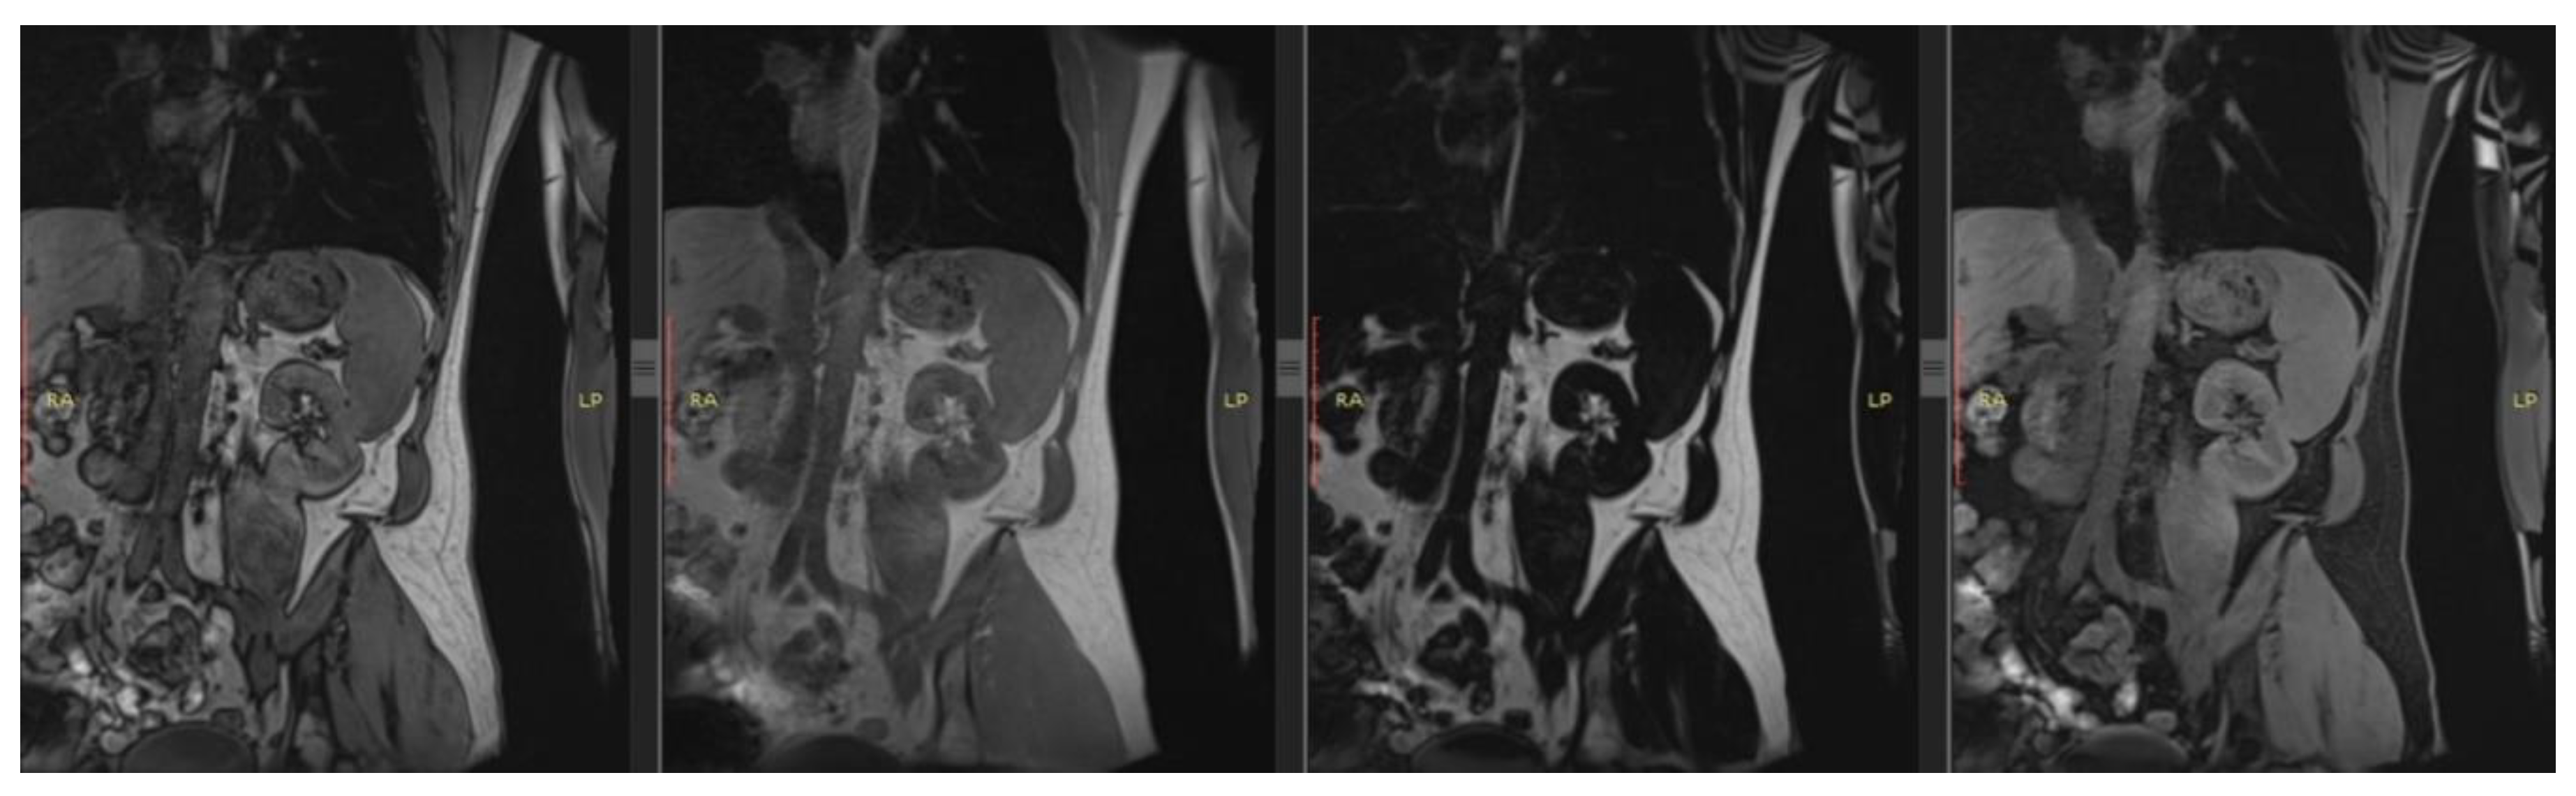

- Wolf, M.; De Boer, A.; Sharma, K.; Boor, P.; Leiner, T.; Sunder-Plassmann, G.; Moser, E.; Caroli, A.; Jerome, N.P. Magnetic resonance imaging T1- and T2-mapping to assess renal structure and function: a systematic review and statement paper. Nephrol. Dial. Transplant 2018, 33, II41–II50. [CrossRef]

- Selby, N.M.; Bmbs, B.; Frcp, D.M.; Francis, S.T. Assessment of Acute Kidney Injury using MRI. J. Magn. Reson. Imaging 2025, 61, 25–41. [CrossRef]